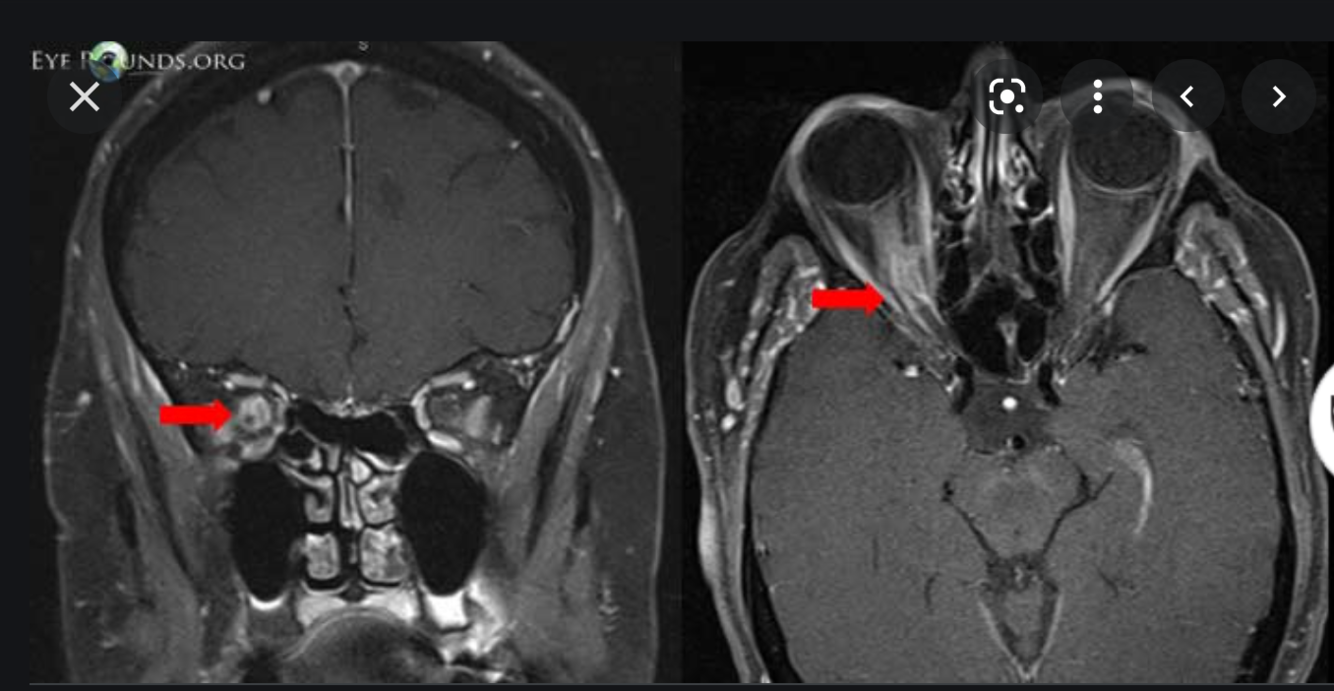

Rad Features of Optic Nerve Meningioma

What are the radiographic findings of ocular melanoma?